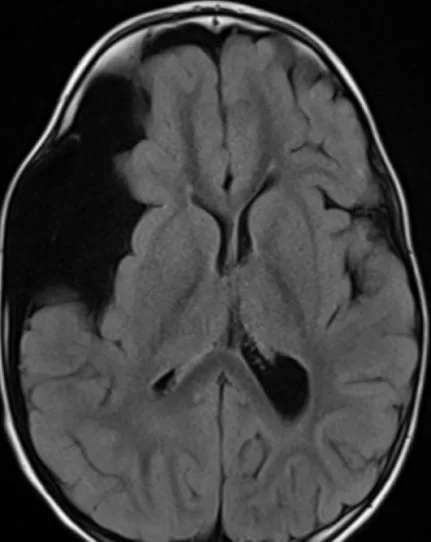

Οι αραχνοειδείς κύστες είναι συλλογές εγκεφαλονωτιαίου υγρού (δηλαδή του υγρού που υπάρχει και κυκλοφορεί φυσιολογικά στον εγκέφαλο και τον σπονδυλικό σωλήνα) εντός της αραχνοειδούς μεμβράνης (Εικόνα 1). Ο μηχανισμός δημιουργίας και αύξησης της κύστης δεν είναι απολύτως σαφής.

Η διάγνωση μπαίνει με τις απεικονιστικές εξετάσεις, και κυρίως με τη μαγνητική τομογραφία, η οποία θα δείξει μιά κύστη γεμάτη με εγκεφαλονωτιαίο υγρό η οποία συνήθως δεν προσλαμβάνει σκιαγραφικό μετά τη χορήγηση σκιαγραφικής ουσίας.